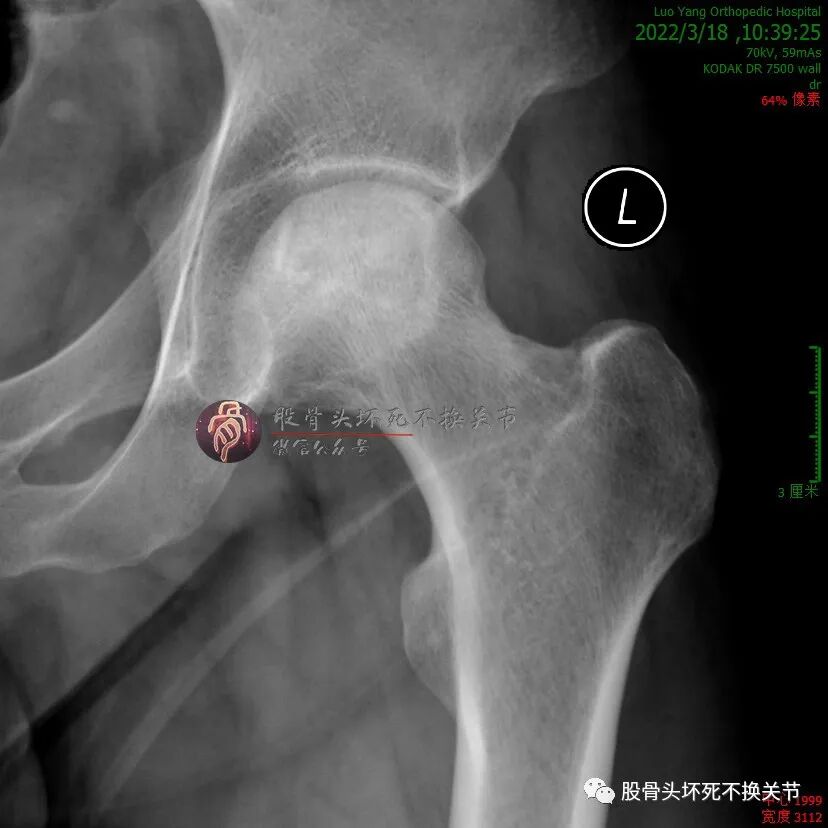

但是,疼痛缓解给予病人莫大希望,开始定期门诊治疗(不用住院、随治随走那种),半年后复查:

这次复查比初次就诊时明显好转,骨密度明显提高,疼痛基本全无,恢复一般的生活、工作能力。